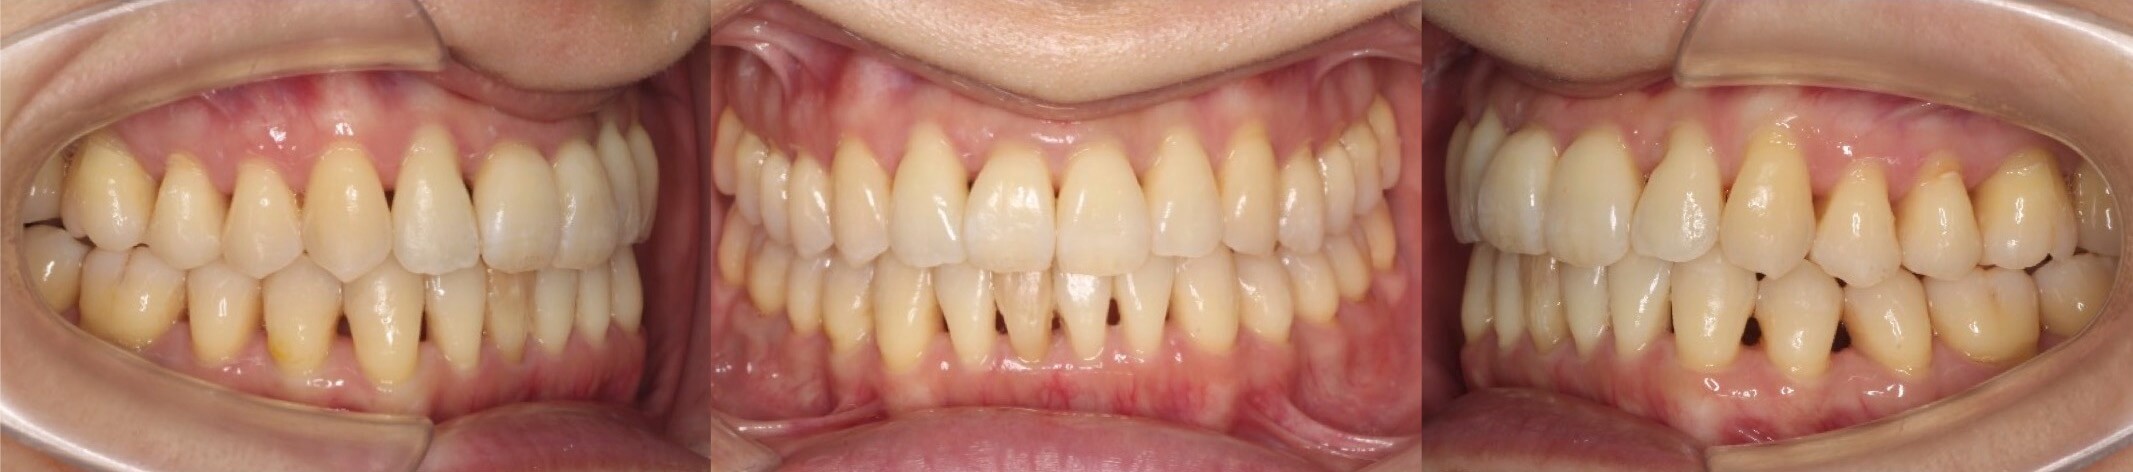

43歳女性・唇側矯正装置・抜歯

ミドルエイジの矯正治療で抜歯方針を選択する場合は、細心の注意を払います。これは、前歯が後方に引き下がりすぎる可能性があるからです。事前に横顔のシミュレーションを確認していただき、ほうれい線が深くなるなどのリスクも承諾の上、治療を開始しました。治療後はバランスの良い横顔になりました。

<症例概要>

主訴:口元の突出

年齢・性別:43歳女性

住まい:千葉県八千代市

症状:上下顎前歯唇側傾斜・正中離開

治療方針:上下左右4番(計4本)

治療装置:唇側矯正装置

固定装置:ナンスホールディングアーチ

治療期間:2年9か月

リテーナー:上下フィックス+プレートタイプ

治療費用:968,000(税込)

代表的副作用:痛み・治療後の後戻り・歯根吸収・歯髄壊死・歯肉退縮

▶︎その他の副作用